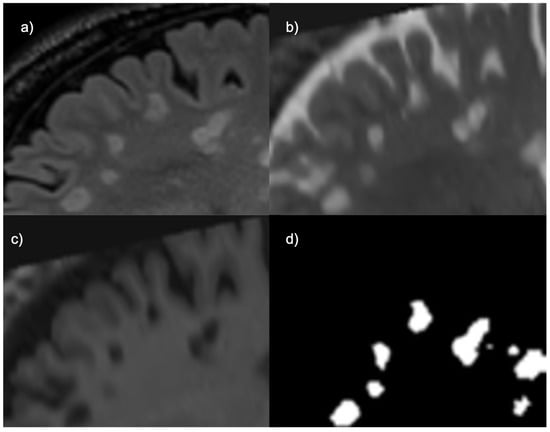

The ground truth for the UMCL dataset had been created by consensus among three different raters (Figure 2), and the ground truth for the MSSEG 2016 dataset had been created using segmentations from seven different raters. Since the presence of more expert raters creates higher intervariability, the creators of the MSSEG 2016 dataset had used the Logarithmic Pool Based STAPLE algorithm to provide a consensus ground truth [26].

Figure 2. Manual segmentation pipeline from UMCL dataset [25].